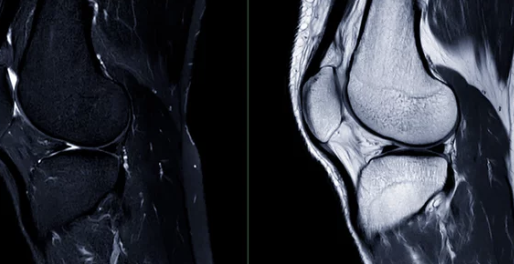

MRI 검사는 X-ray나 CT보다 더욱 정밀하게 뼈, 근육, 인대, 신경 등 연부 조직을 확인할 수 있어 다양한 질환 진단에 활용됩니다. 하지만 비싼 비용 때문에 검사를 망설이는 분들도 많으실 텐데요.

MRI 검사는 자기장과 고주파를 이용하여 인체 내부를 영상화하는 검사 방법으로, X-ray나 CT보다 더욱 정밀하게 연부 조직을 확인할 수 있습니다.

- 무릎, 어깨, 손목, 발목 관절 질환:

- 반월상 연골판 파열

- 십자인대 파열

- 무릎 MRI: 10만원 ~ 20만원 (외래 기준)